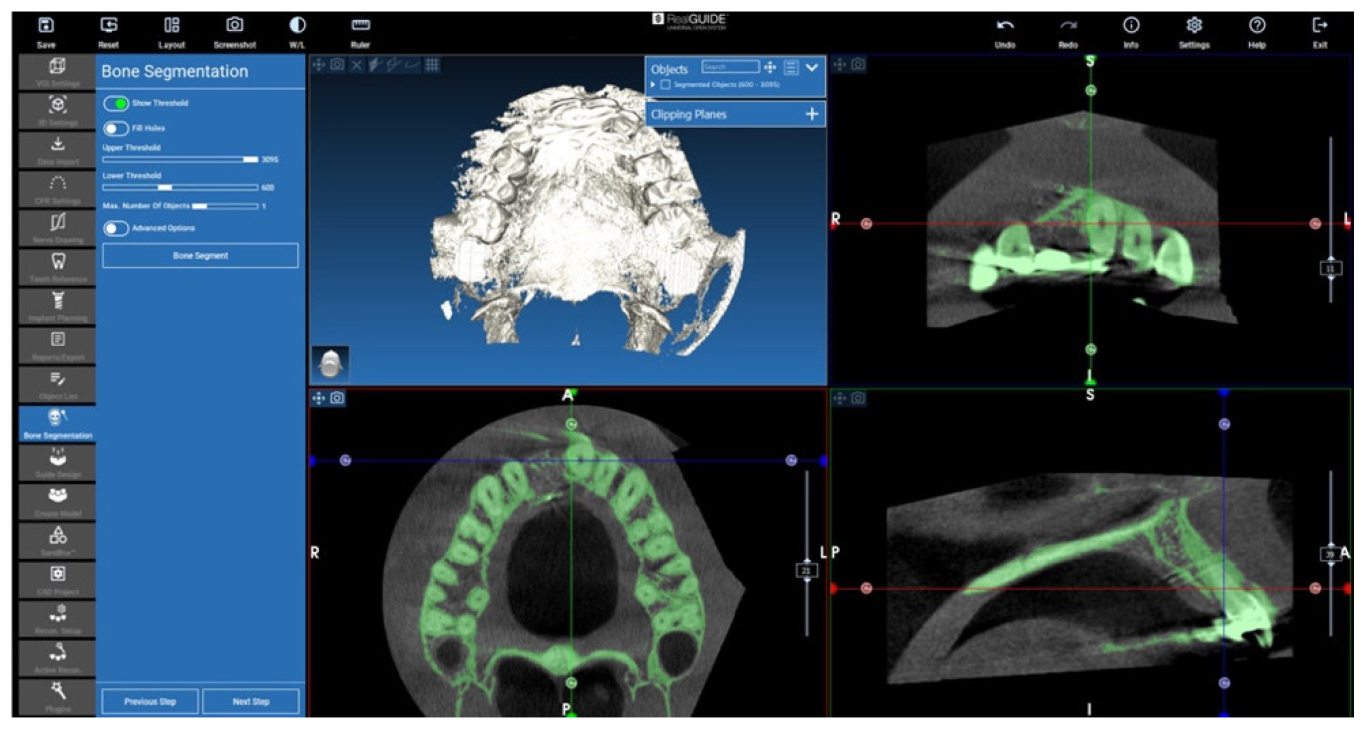

2.2. D-Evaluation Procedure

2.3. Cone Beam CT Conversion to STL by Means of Segmentation

2.4. Isolation of the Augmented Area

2.5. Evaluation of the Volumes